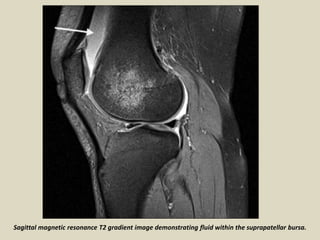

Sagittal magnetic resonance T2 gradient image demonstrating fluid within the suprapatellar bursa.

Suprapatellar bursitis. A 29-year-old male presented with internal derangement of the knee: sagittal proton

density fat saturated (A) and axial T2W gradient-echo (B) images show a distended suprapatellar bursa

(arrows) and in addition, a partial tear of the anterior cruciate ligament (thick arrow in A)